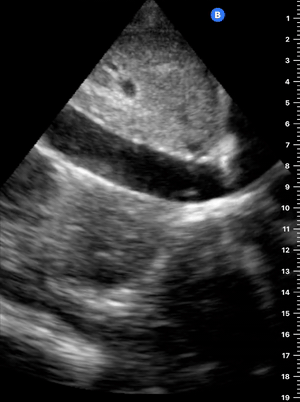

THE VIEWS

The PLAX view is versatile and allows the recognition of multiple landmarks, making it good for visual estimation of LV contractility. It is essential to optimize the view ensuring a true sagittal long axis, as being oblique to the LV chamber may underestimate its size and overestimate its emptying. The PSAX view at the level of the papillary muscles reveals the entire muscular circumference and concentric squeeze of the LV. It is useful to estimate both global function and focal wall motion abnormalities. The A4C view, although technically challenging, provides good insight into the global myocardial function and chamber size.

LV CONTRACTILITY

Qualitative assessment of the LV and visual estimation of Ejection Fraction is based on three parameters:

Endocardial excursion.

Myocardial thickening.

Movement of the anterior leaflet of the mitral valve.

A qualitative assessment is typically categorised as:

Normal (LVEF 50-65%)

Moderately Depressed (LVEF 30-50%)

Severely Depressed (LVEF < 30%)

Hyperdynamic (LVEF > 65%)

E-POINT SEPTAL SEPARATION

Active movement of the MV anterior leaflet during diastole, so it nearly touches the septum, correlates with good LV filling and ejection fraction. This can be assessed objectively by measuring the E-point septal separation (EPSS), which is the distance between the septum and the mitral anterior leaflet either in B-mode or M-mode. EPSS < 7mm is considered normal. EPSS is a good surrogate measure of ejection fraction, but it should be used with caution, as septal hypertrophy and mitral valve stenosis can lead to wrong estimations. In the PLAX view, it is important to have the septum lying horizontally flat on the image, as an oblique orientation may result in an overestimation of the EPSS.

Depiction of E-point septal separation: M-mode is used to measure the distance between the open mitral valve and the ventricular septum. Measurements greater than 7 mm are suggestive of depressed systolic ejection. (1. RV free wall, 2. Interventricular septum, 3. Mitral valve, 4. LV free wall). From: The "5Es" of emergency physician-performed focused cardiac ultrasound (11).